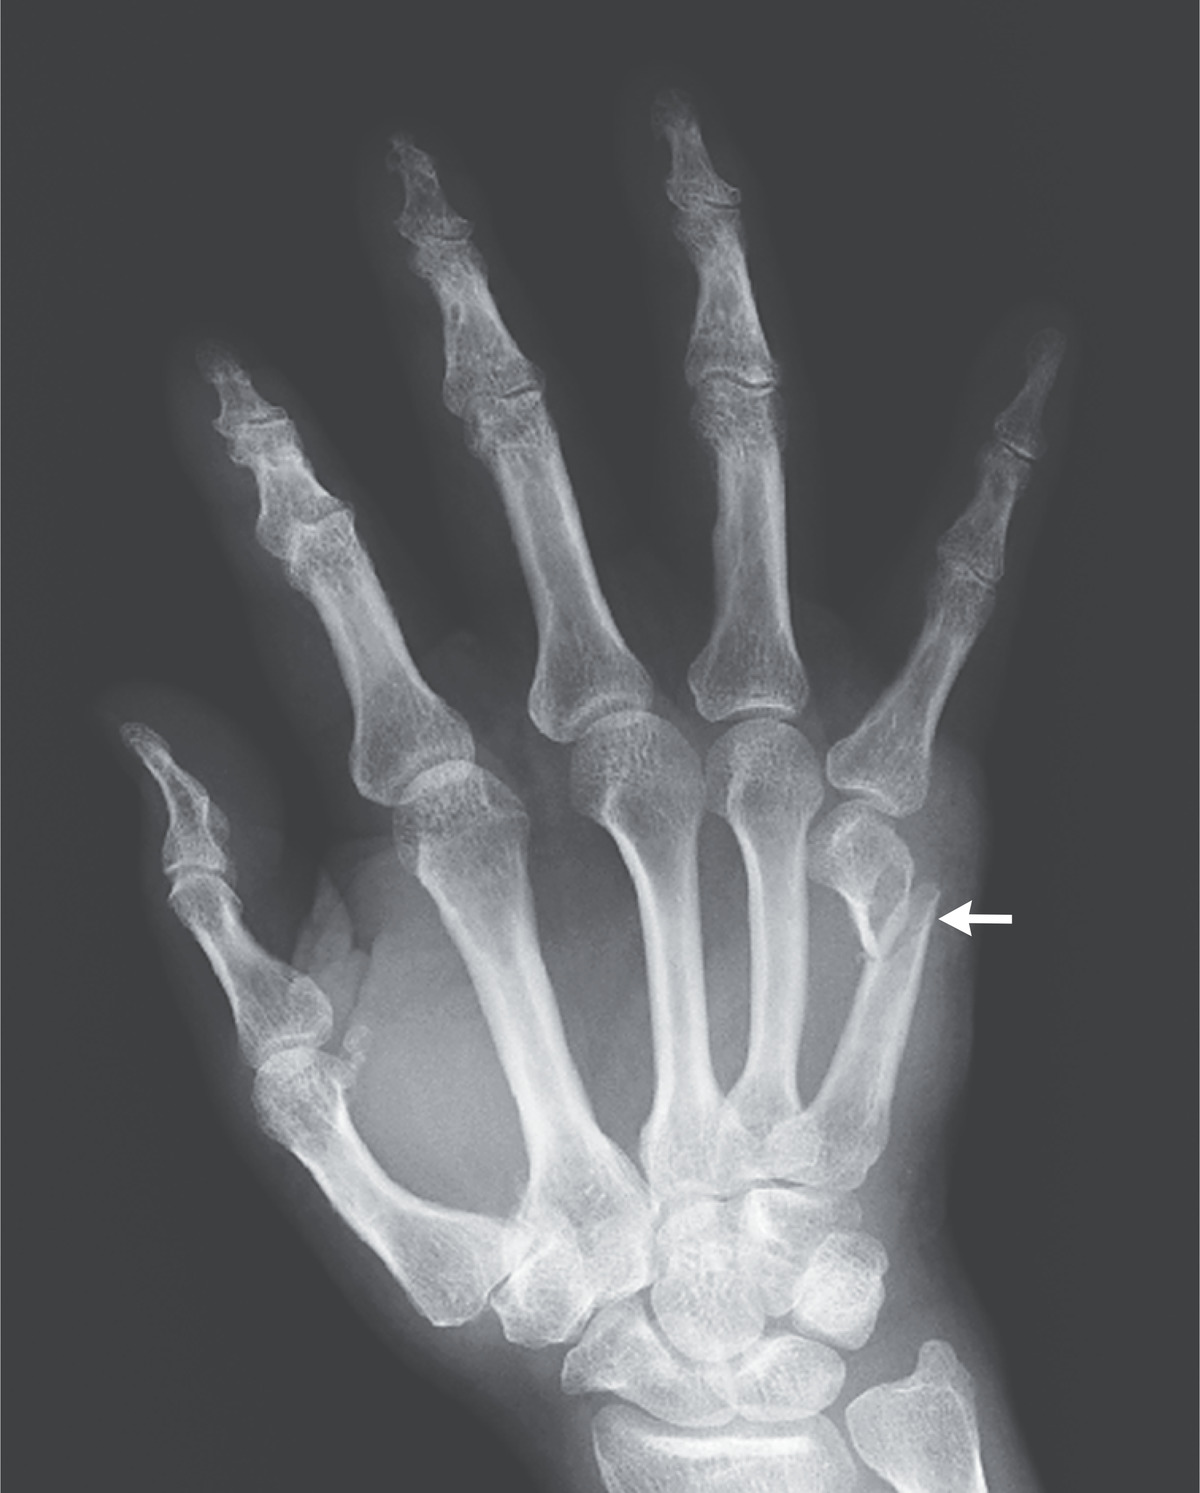

Boxer fracture. Radiograph shows a fracture of the fifth metacarpal Medical Term For Boxer's Fracture A boxer’s fracture is when you break a bone at the base of your finger, near the knuckle or neck of the bone. Boxer's fractures are common injuries of the 5th metacarpal neck, typically caused by direct trauma such as punching a hard object with a closed fist. It happens when you break the neck of. A boxer’s fracture is. Medical Term For Boxer's Fracture.